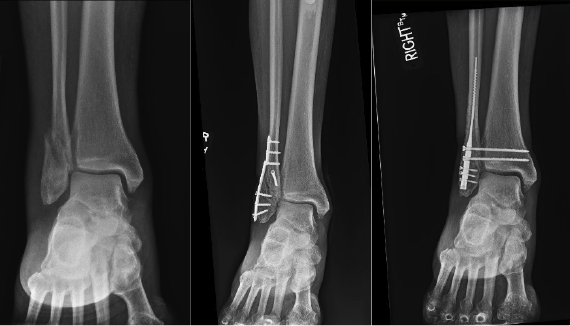

The key question is then, how does the IM nail compare to a more traditional plate and screw construct for fibular fractures? Numerous studies compare the approaches, most of them very recent, as this technique has garnered popularity. Overall, the literature consistently shows lower complication rates with the fibular IM nail.31,39-41 A 2022 level 1 study found sufficient quality of evidence in the current studies available to conclude that there is no clinical difference between the IM nail and ORIF 12 months postoperatively.42 With that being said, there were reduced complications with the IM nail as previously discussed, and no difference in union rates42 (Figure 2).

As previously discussed, multiple demographics may find benefit with the fibular IM nail, especially those at high risk.22 In contrast, a 2021 retrospective comparative study looked at patients between 18 and 50 years old with AO-OTA 44B or C fractures (Weber B and C included) who participated in sports or higher-level activities.43 They found the IM nail group had poorer radiographic reduction on CT compared to ORIF, especially in Weber C, PER, trimalleolar, and comminuted fibula injuries. Although reduction was not as good with the fibular nail, there were significantly fewer complications and there were no differences in clinical outcomes between groups. While the IM nail may not always provide the same reduction as ORIF, the clinical outcomes differences are negligible indicating the IM nail is an adequate option compared to ORIF in young, active patients.44 Of note, we suspect newer advances in fibular IM fixation will aid in correcting these downfalls and continue to provide adequate patient satisfaction, currently supported by recent literature.20,45-50

At this time, plate fixation does appear to be superior for anatomic reduction as discussed,41 but further studies are required to assess for any significant long-term negative sequelae after IM fixation of the fibula. Overall, there is a lower risk of implant removal, lower complications, and earlier return to weight-bearing in the appropriate patient with IM fixation of distal fibular fractures.49,51-53 Newer literature suggests the possibility of achieving sufficient syndesmotic stabilization through the utilization of IM fixation, thereby potentially broadening its already expanding range of indications.12,54